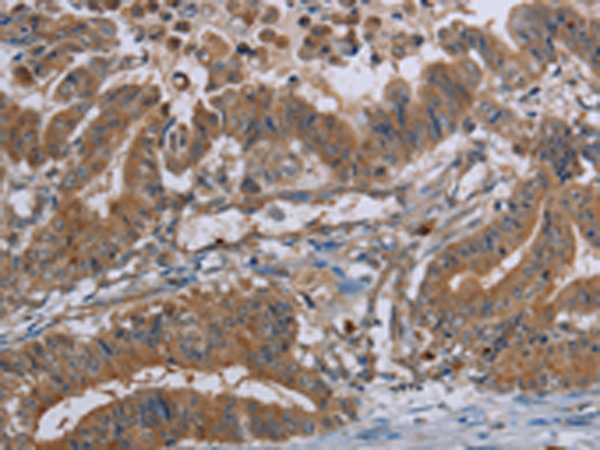

分类: 科研抗体货号: P01553别名: ATLD; HNGS1; MRE11A; MRE11B应用: WB,IHC反应种属: Human, Mouse, Rat